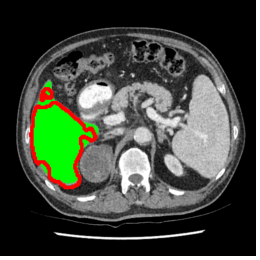

Our primary findings comparing the proposed model to baseline fully-supervised models when segmenting the liver from the LiTS dataset are reported in Table 1. The reported results demonstrate that our SAM-Mix model consistently achieves higher Dice scores compared to the fully supervised baselines as well as the two-stage SAM-PP method. Against U-Net, the best-performing fully supervised method, the SAM-Mix variant trained on 50 segmentation labeled slices (SAM-Mix-50), achieves a Dice score improvement of 5.9%. In terms of Hausdorff distance, while the fully-supervised baselines do slightly outperform SAM-Mix-5 and SAM-Mix-100, SAM-Mix-50 does achieve a lower Hausdorff distance by 22.38%. Qualitative evaluation as shown in Figs. 3 further affirms the superiority of SAM-Mix over baseline and existing fully-supervised methods as well as the two-stage SAM-PP variants. Furthermore, the boxplot visualization in Fig. 2 showcases consistently improved performance by SAM-Mix outperforming all the fully supervised and semi-supervised methods.

To test the generalizability of SAM-Mix, we validate it on a cross-domain dataset (TotalSegmentator). As reported in Table 2, the segmentation performance of SAM-Mix on the cross-domain task is as promising as the in-domain results. Despite the data shifts, from LiTS to TotalSegmentator, SAM-Mix outperforms all of the baseline models in terms of generalizability, by significant margins. SAM-Mix-50 achieves a Dice score improvement of 25.4%, and a lower Hausdorff distance by 62.26% compared to the best-performing full-supervised U-Net model. These results further validate the few-shot capabilities and establish our SAM-Mix as a well-generalized tool for medical image segmentation.